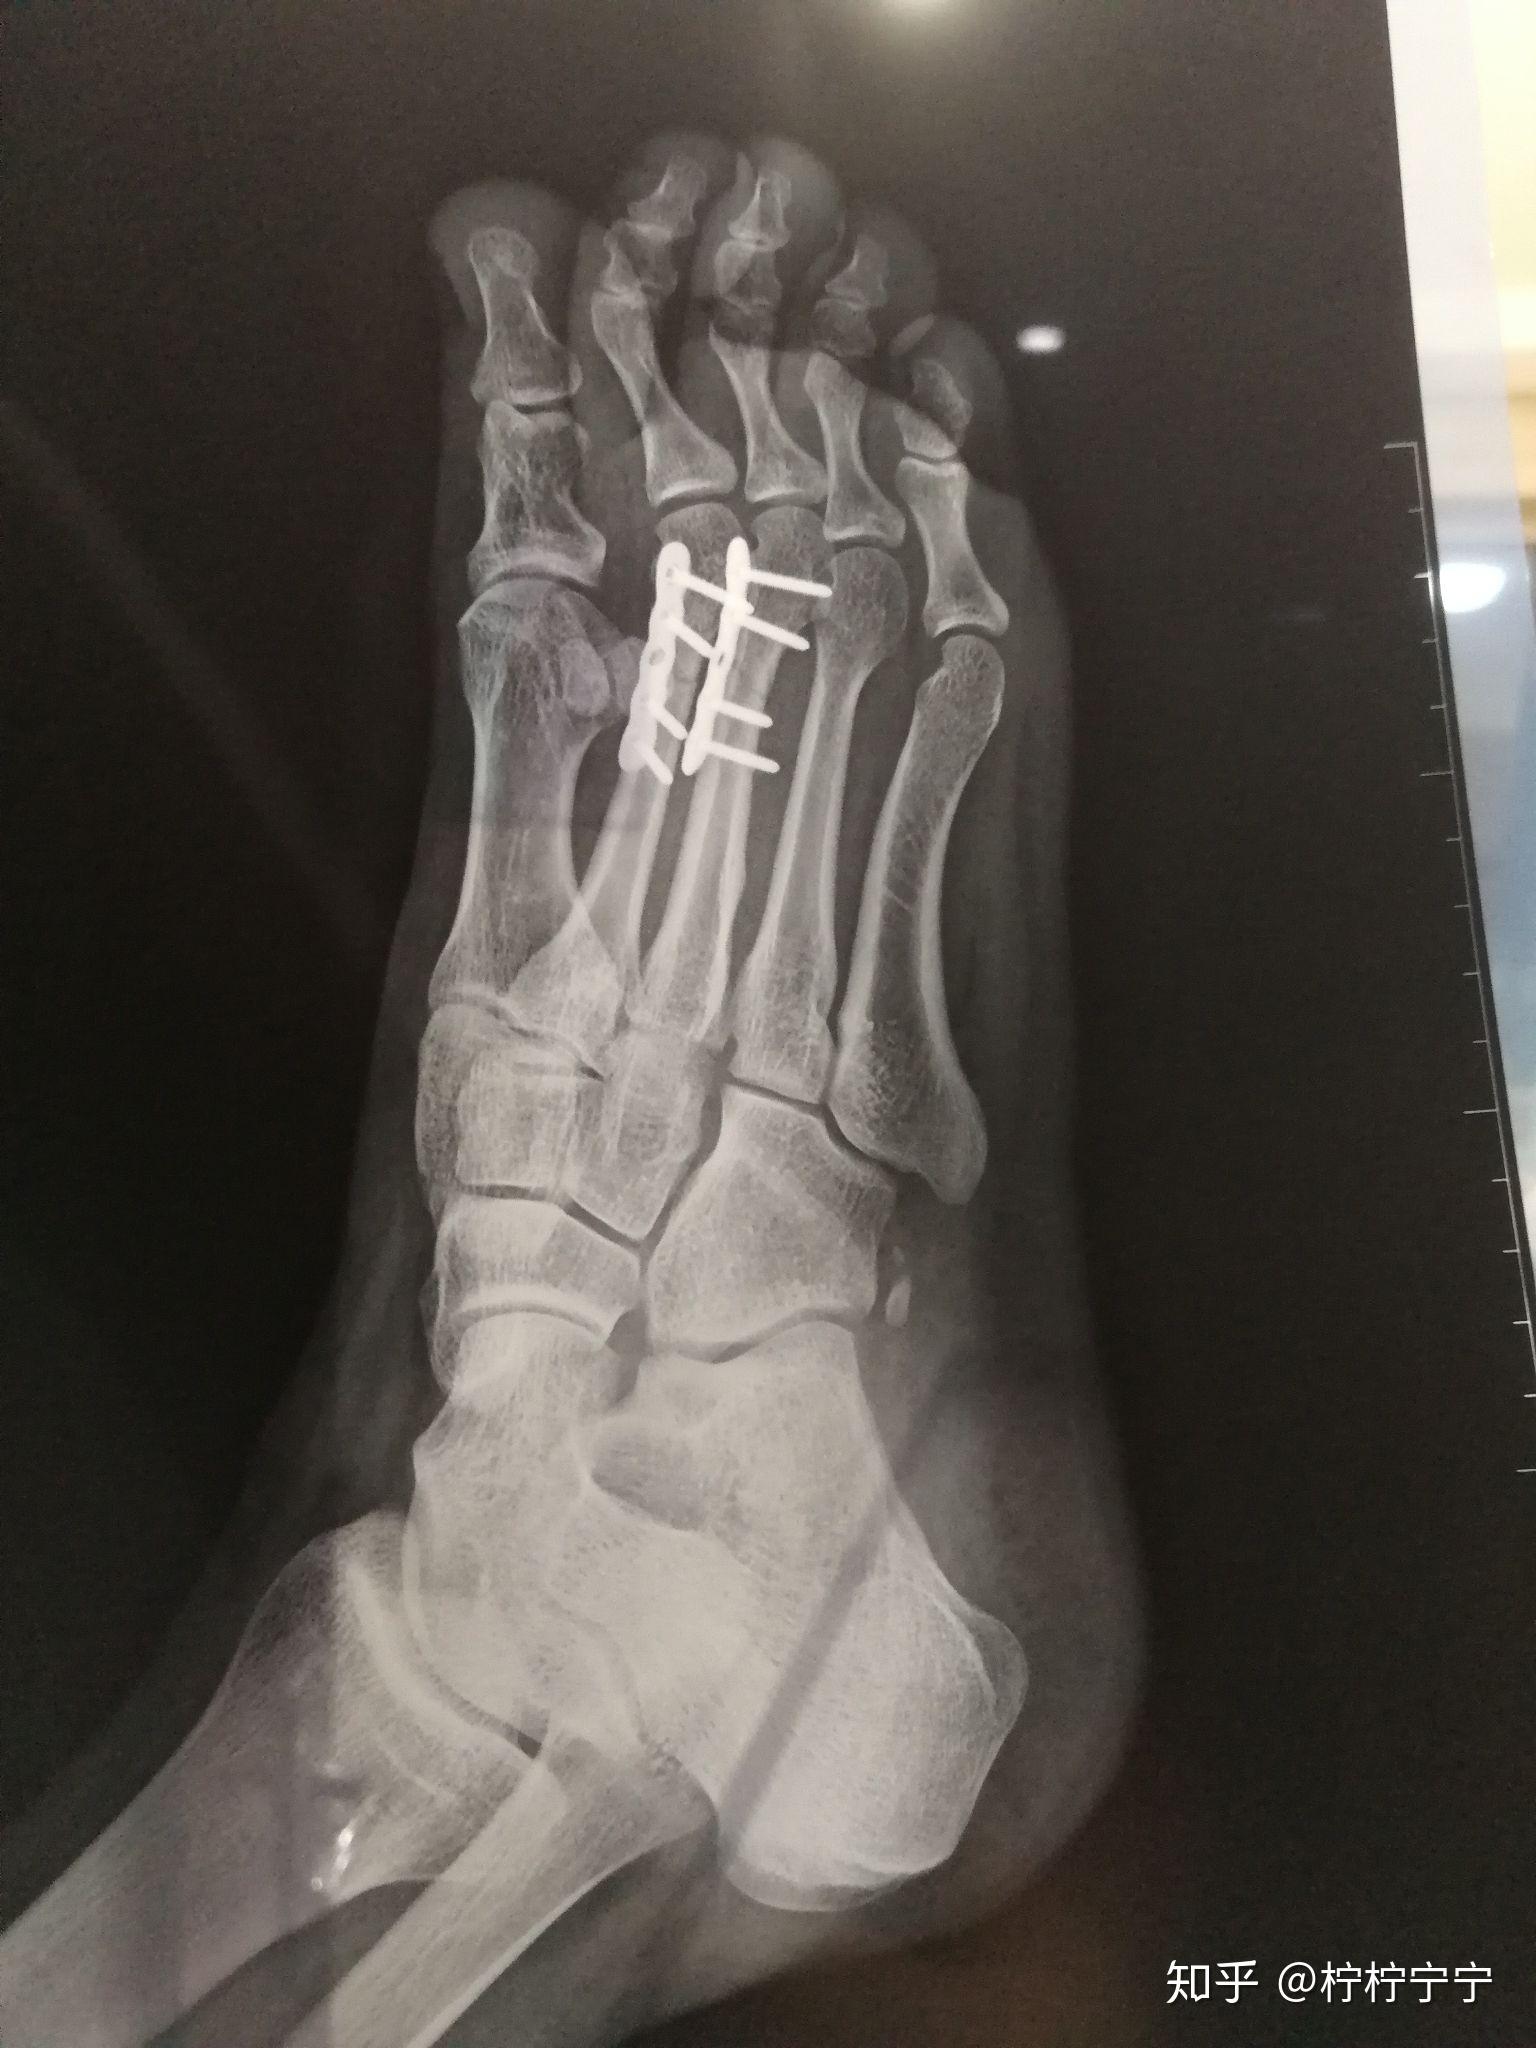

左脚第二跖骨骨折需要多久才能正常走路? - 知乎

看看第二跖骨粉碎性骨折手术怎么做